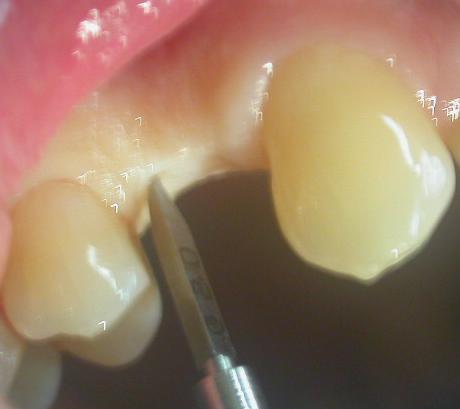

Previa anestesia locale di superficie, senza effettuare un lembo mucoperiosteo, quindi nessun bisturi, effettuiamo un’osteotomia iniziale di 5 mm. in cresta ossea con una fresa a lancia, segue una seconda fresa di Ø 2,00 mm. e dell’altezza stabilita in base al minimpianto da utilizzare.

( figura 2-3-4-5 )